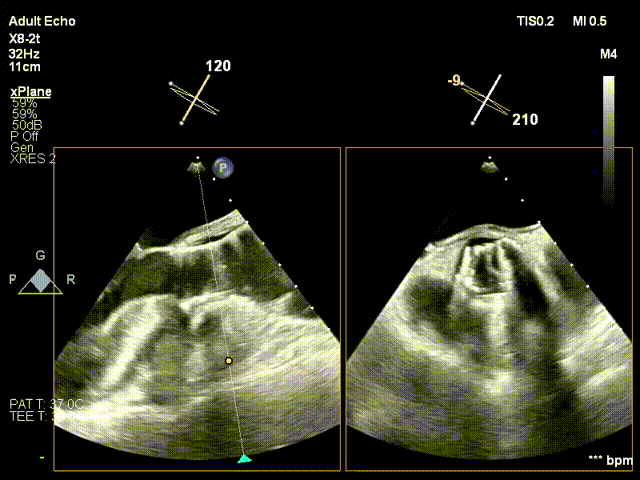

术前、术后超声对比

术前

术后超声显示瓣口未见明显反流,无瓣周漏,主动脉瓣前向血流加速Vmax=1.65m/s,有效开口面积1.61cm²,PGmean=4mmHg。术后监测,心率心电正常,无传导阻滞。患者生命体征稳定。本次手术植入瓣膜定位准确,操作简便,症状即刻改善,手术圆满成功。